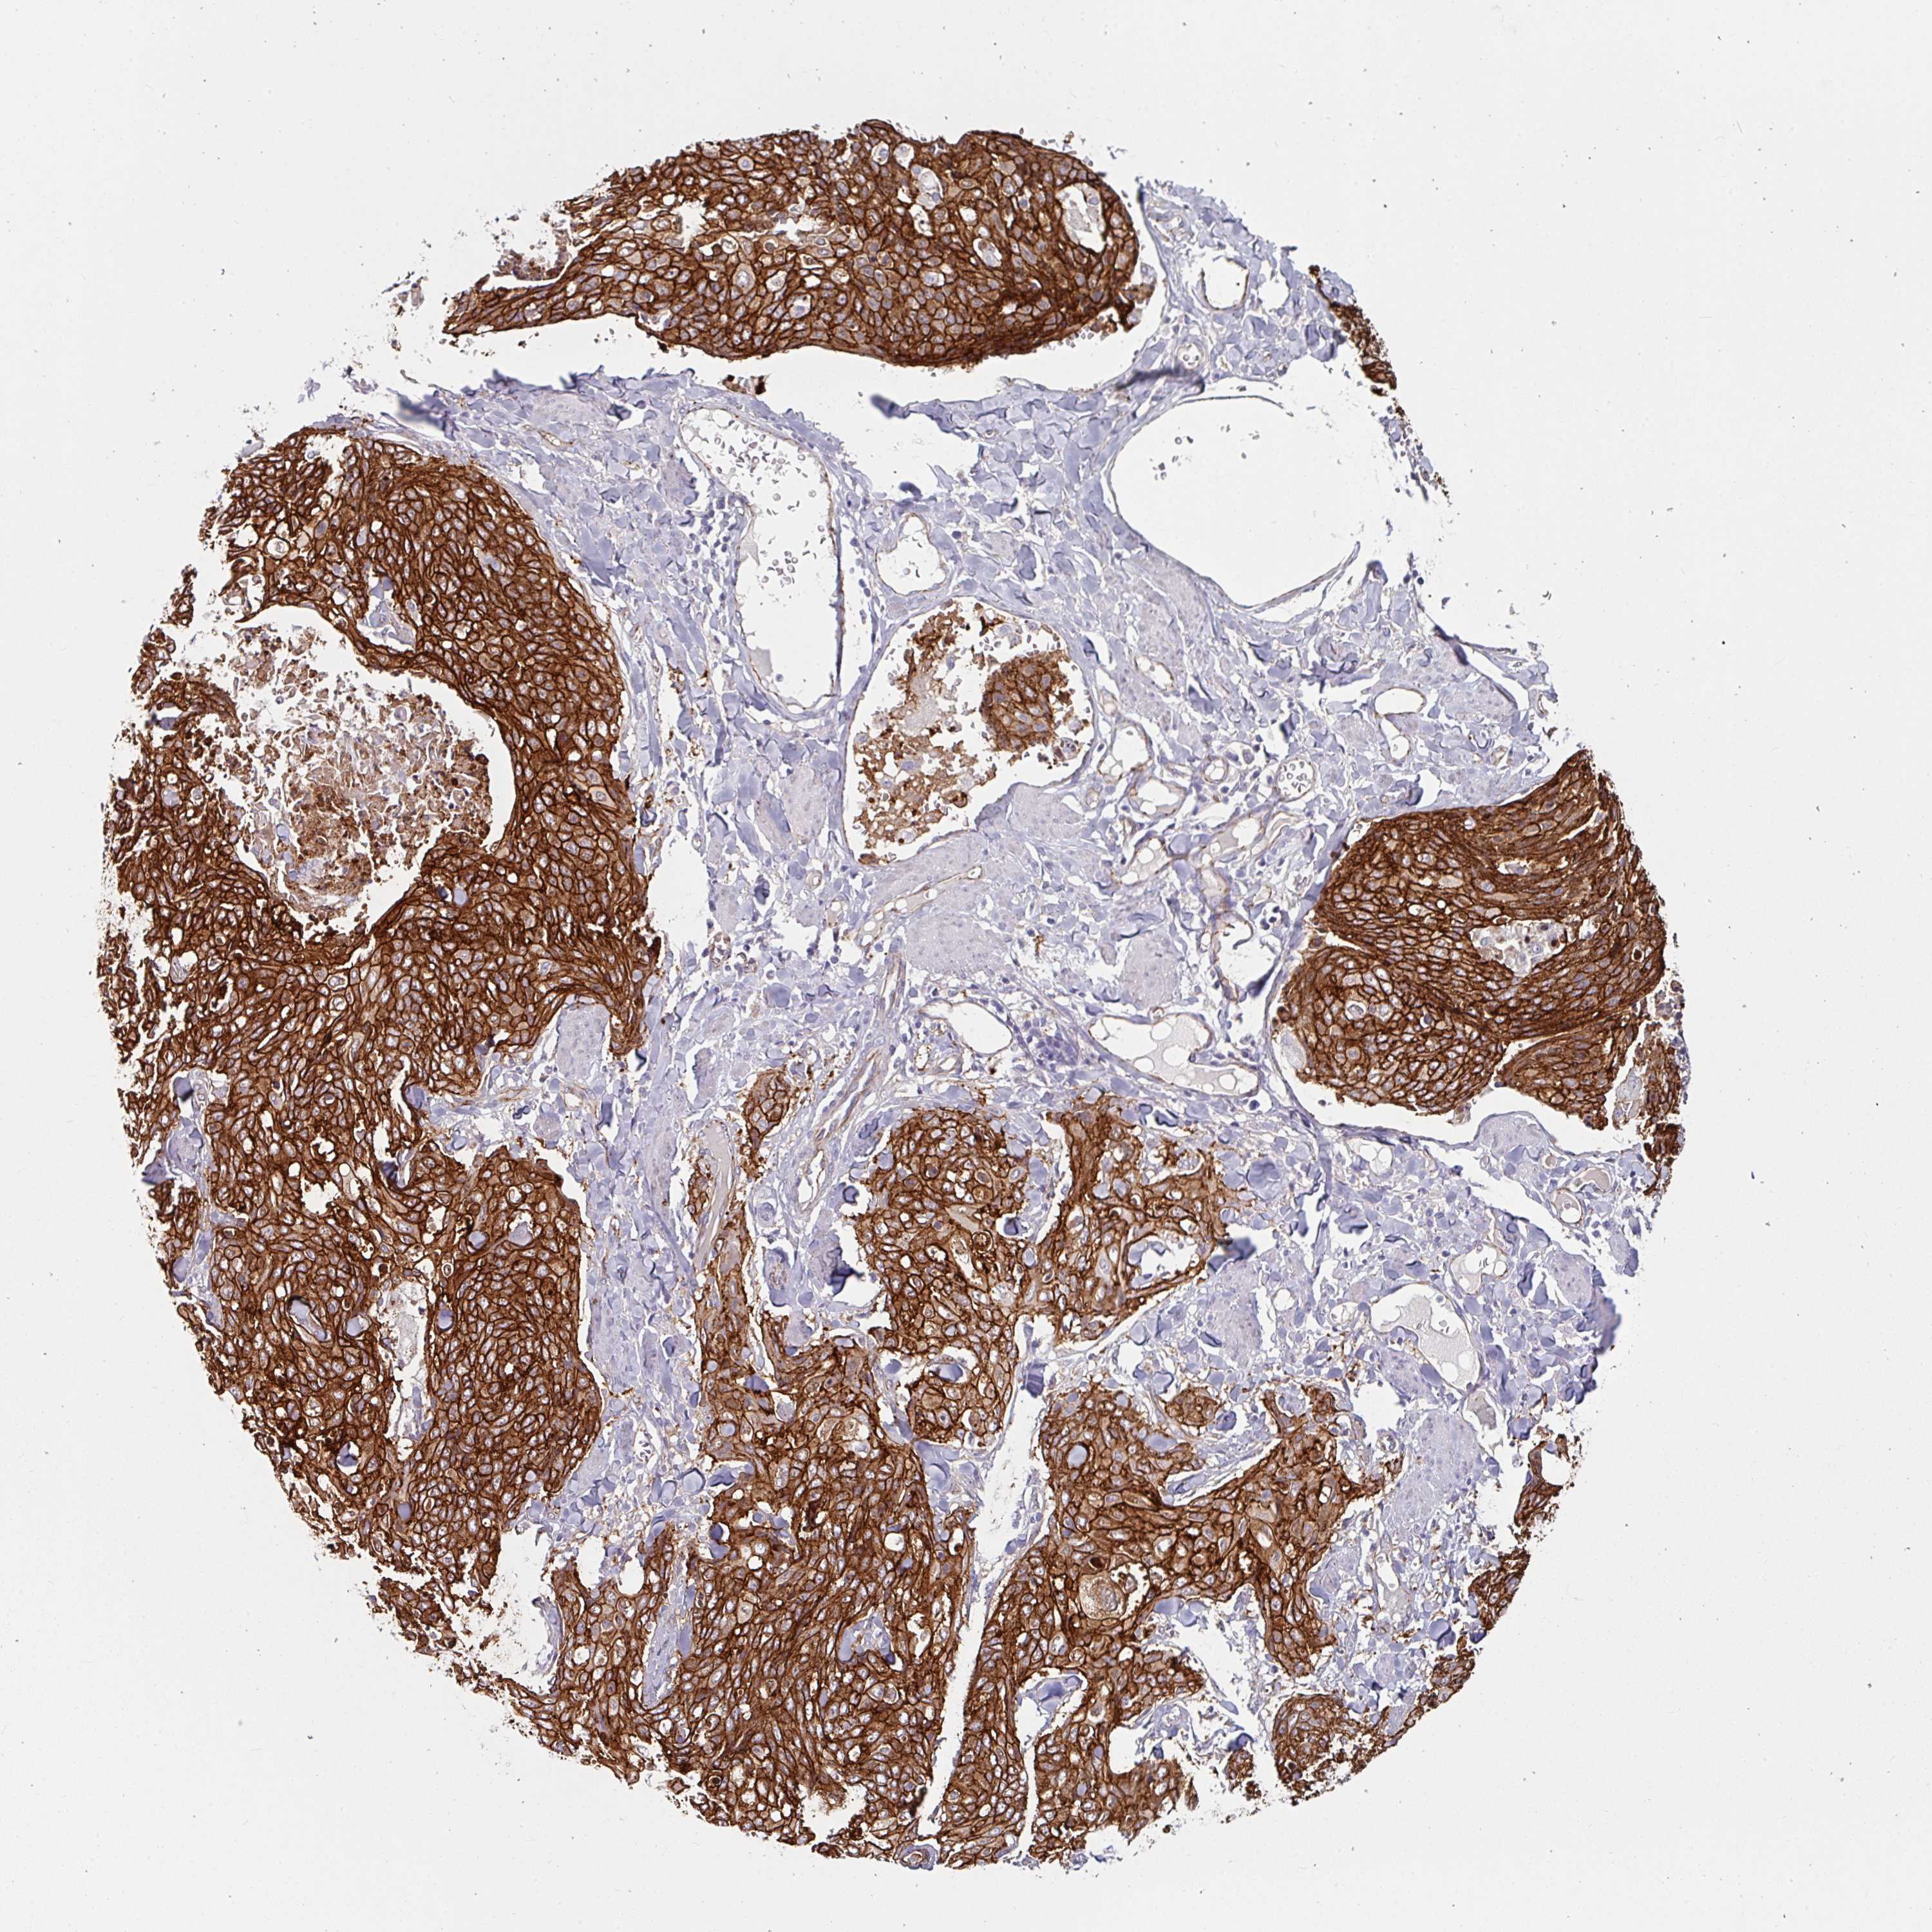

SKIN CANCER - Protein expressioni

A mouse-over function shows sample information and annotation data. Click on an image to view it in a full screen mode. Samples can be filtered based on level of antibody staining by selecting one or several of the following categories: high, medium, low and not detected. The assay and annotation is described here.

Antibody stainingi

Antibody staining in the annotated cell types in the current human tissue is reported as not detected, low, medium, or high, based on conventional immunohistochemistry profiling in selected tissues. This score is based on the combination of the staining intensity and fraction of stained cells.

Each image is clickable and will lead to virtual microscopy that enables deeper exploration of all samples and also displays staining intensity scores, fraction scores and subcellular localization as well as patient and tissue information for each sample.

Antibody HPA032047

Antibody CAB002139

Basal cell carcinoma

Squamous cell carcinoma, NOS

Squamous cell carcinoma, metastatic, NOS